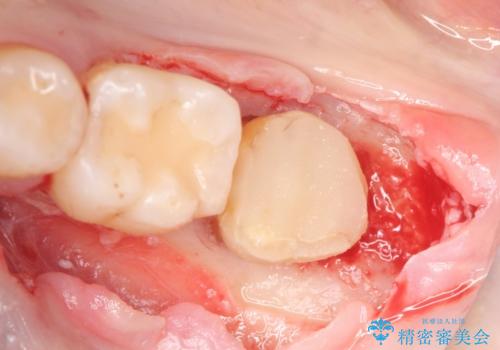

- 左下の一番奥の歯が時折激しく痛むので診て欲しいといらっしゃった方の症例です。以前に他院を受診したところ、そもそも被せ物を入れるスペースがないため抜歯しかないと言われたとのことでした。

診査の結果根尖病変を認めたため再根管治療を行った後に、被せ物を入れるスペースを作るため歯冠延長術を行いました。

歯冠延長術について

歯冠長延長術とは歯肉弁根尖側移動術とも言い、歯の高さが低くクラウン(被せ物)による治療が難しい場合に、歯茎を歯根方向に下げることで歯の高さを確保する手術です。歯の高さが十分にあることで、外れにくいしっかりとしたクラウンを被せることができます。